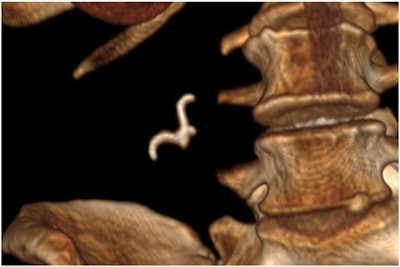

To identify the object and potential for perforation, they obtained a 3D CT reconstruction. The reconstruction showed the foreign object had a sharp hook that could perforate the bowel loop, so they opted to remove it surgically.